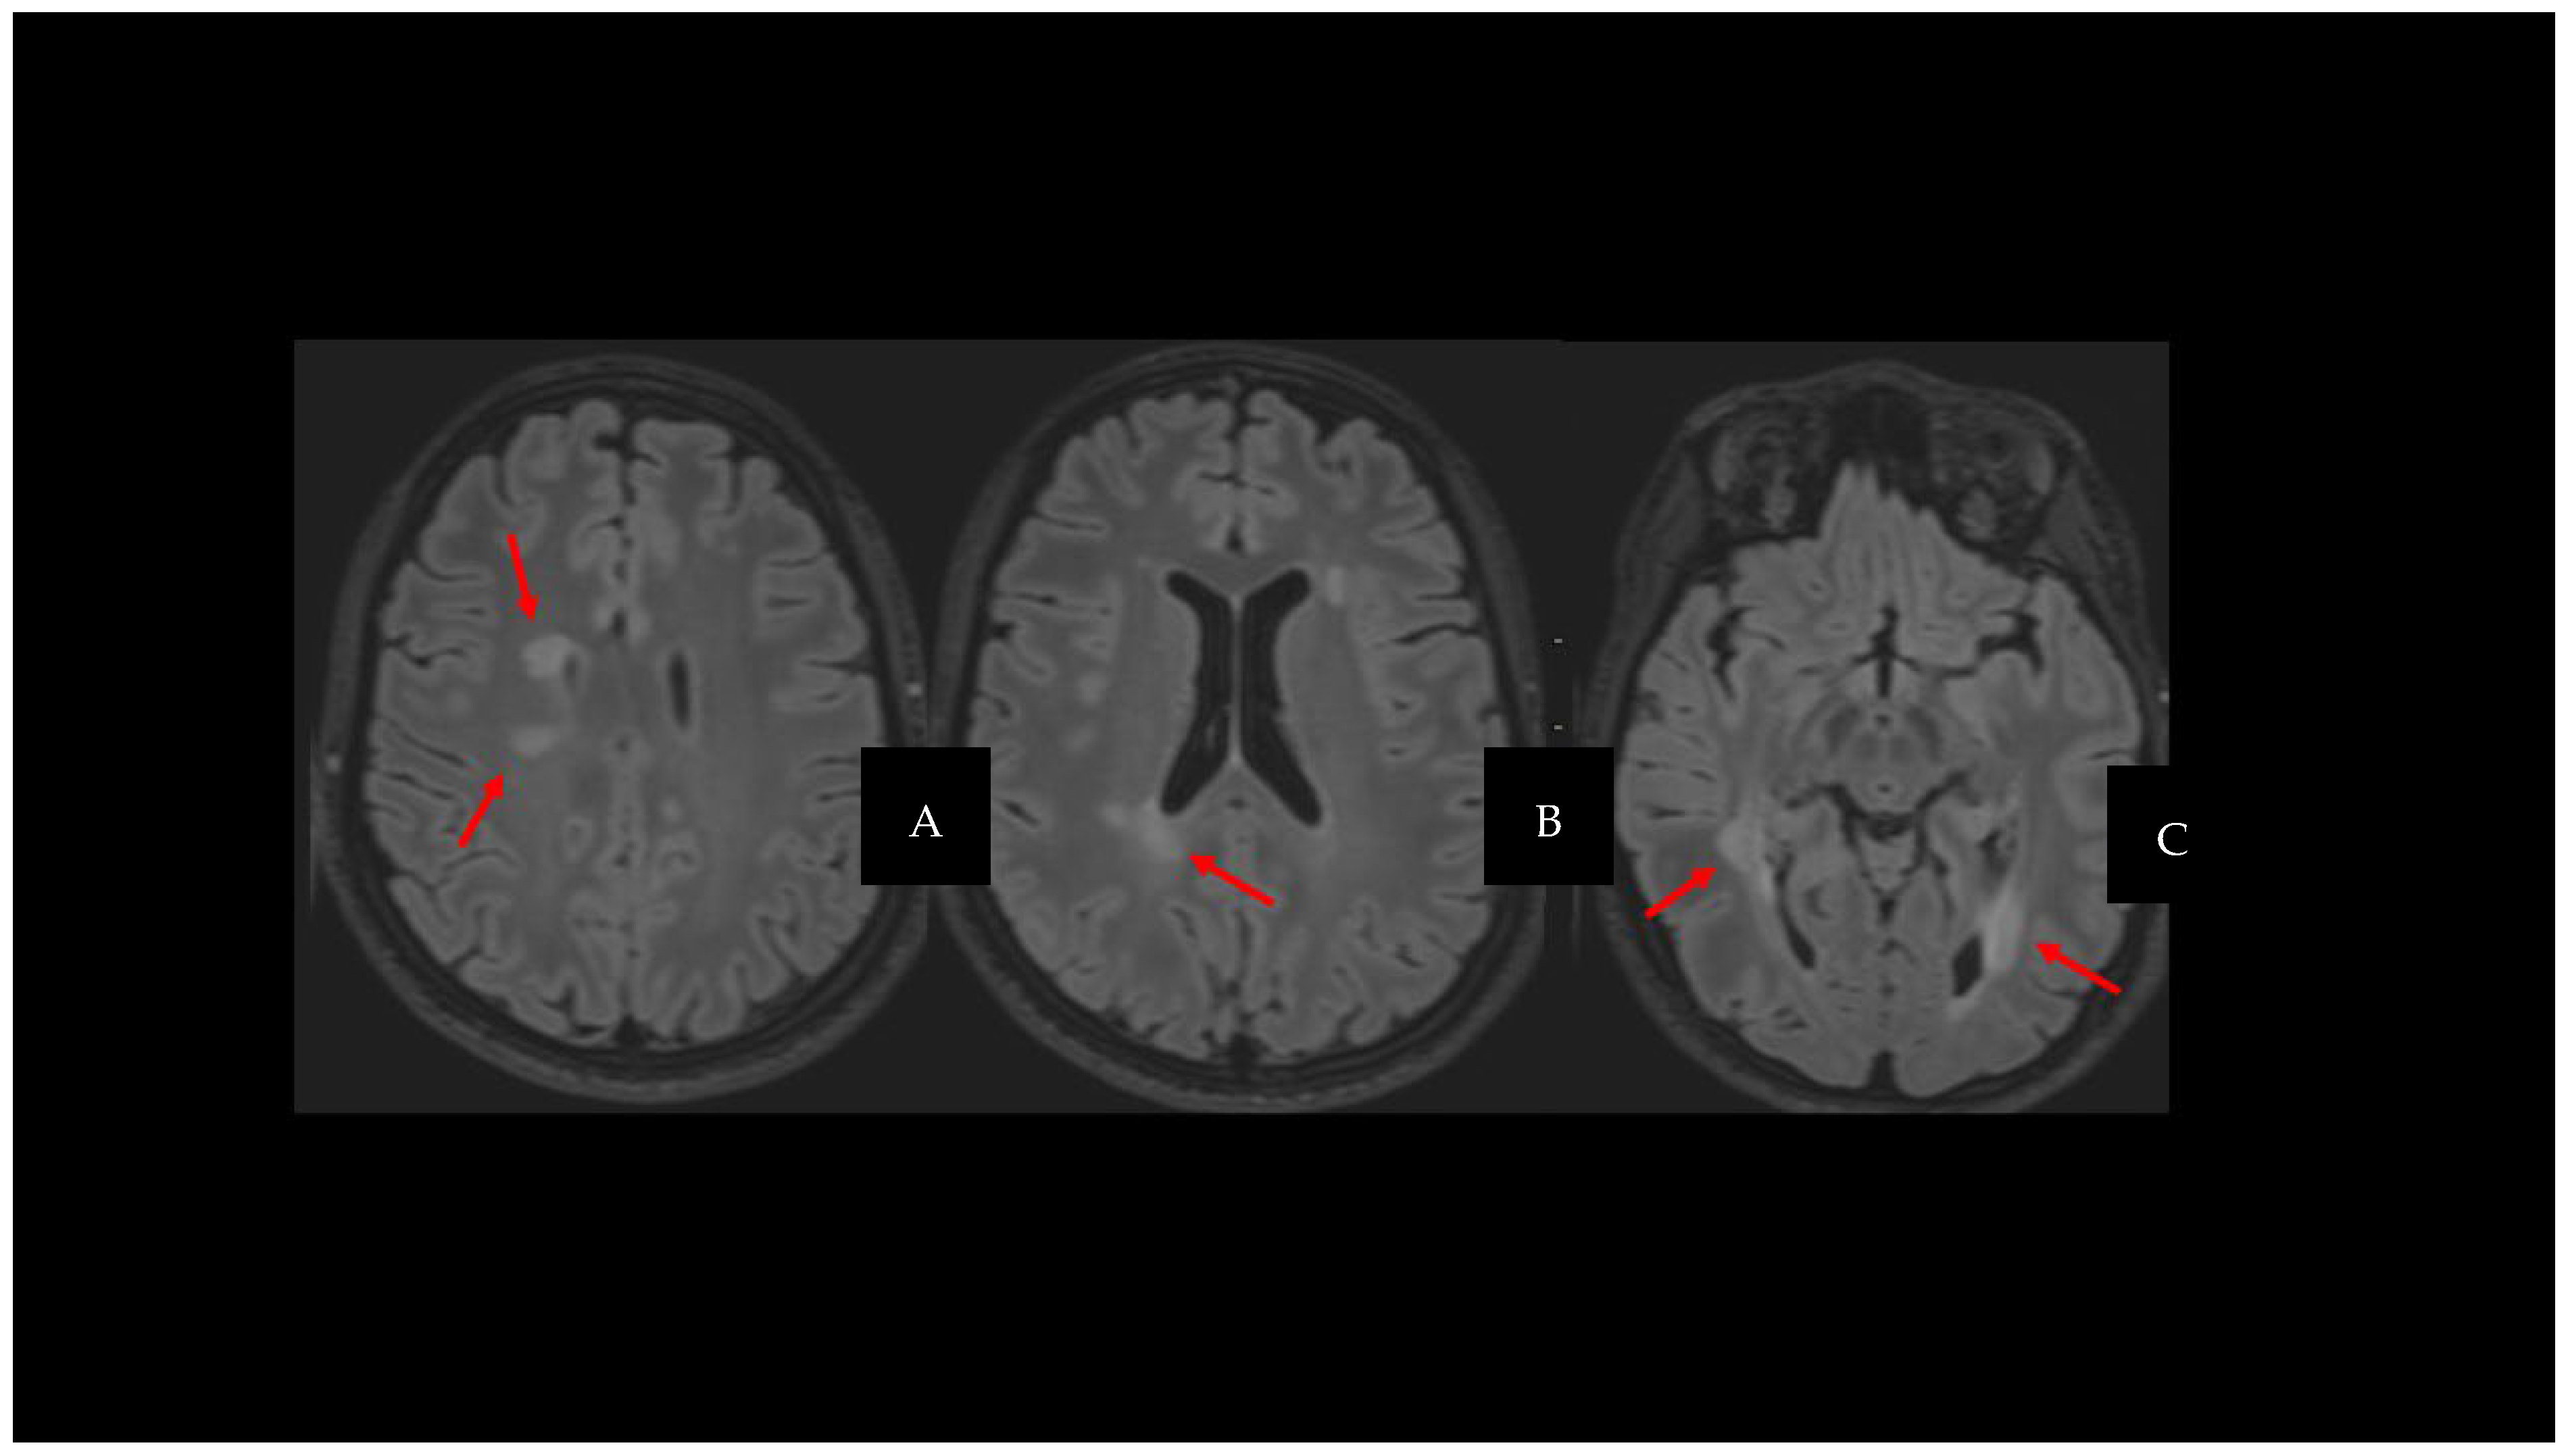

2. Cortical Lesions

3. Iron-Derived Imaging and Chronic Inflammation